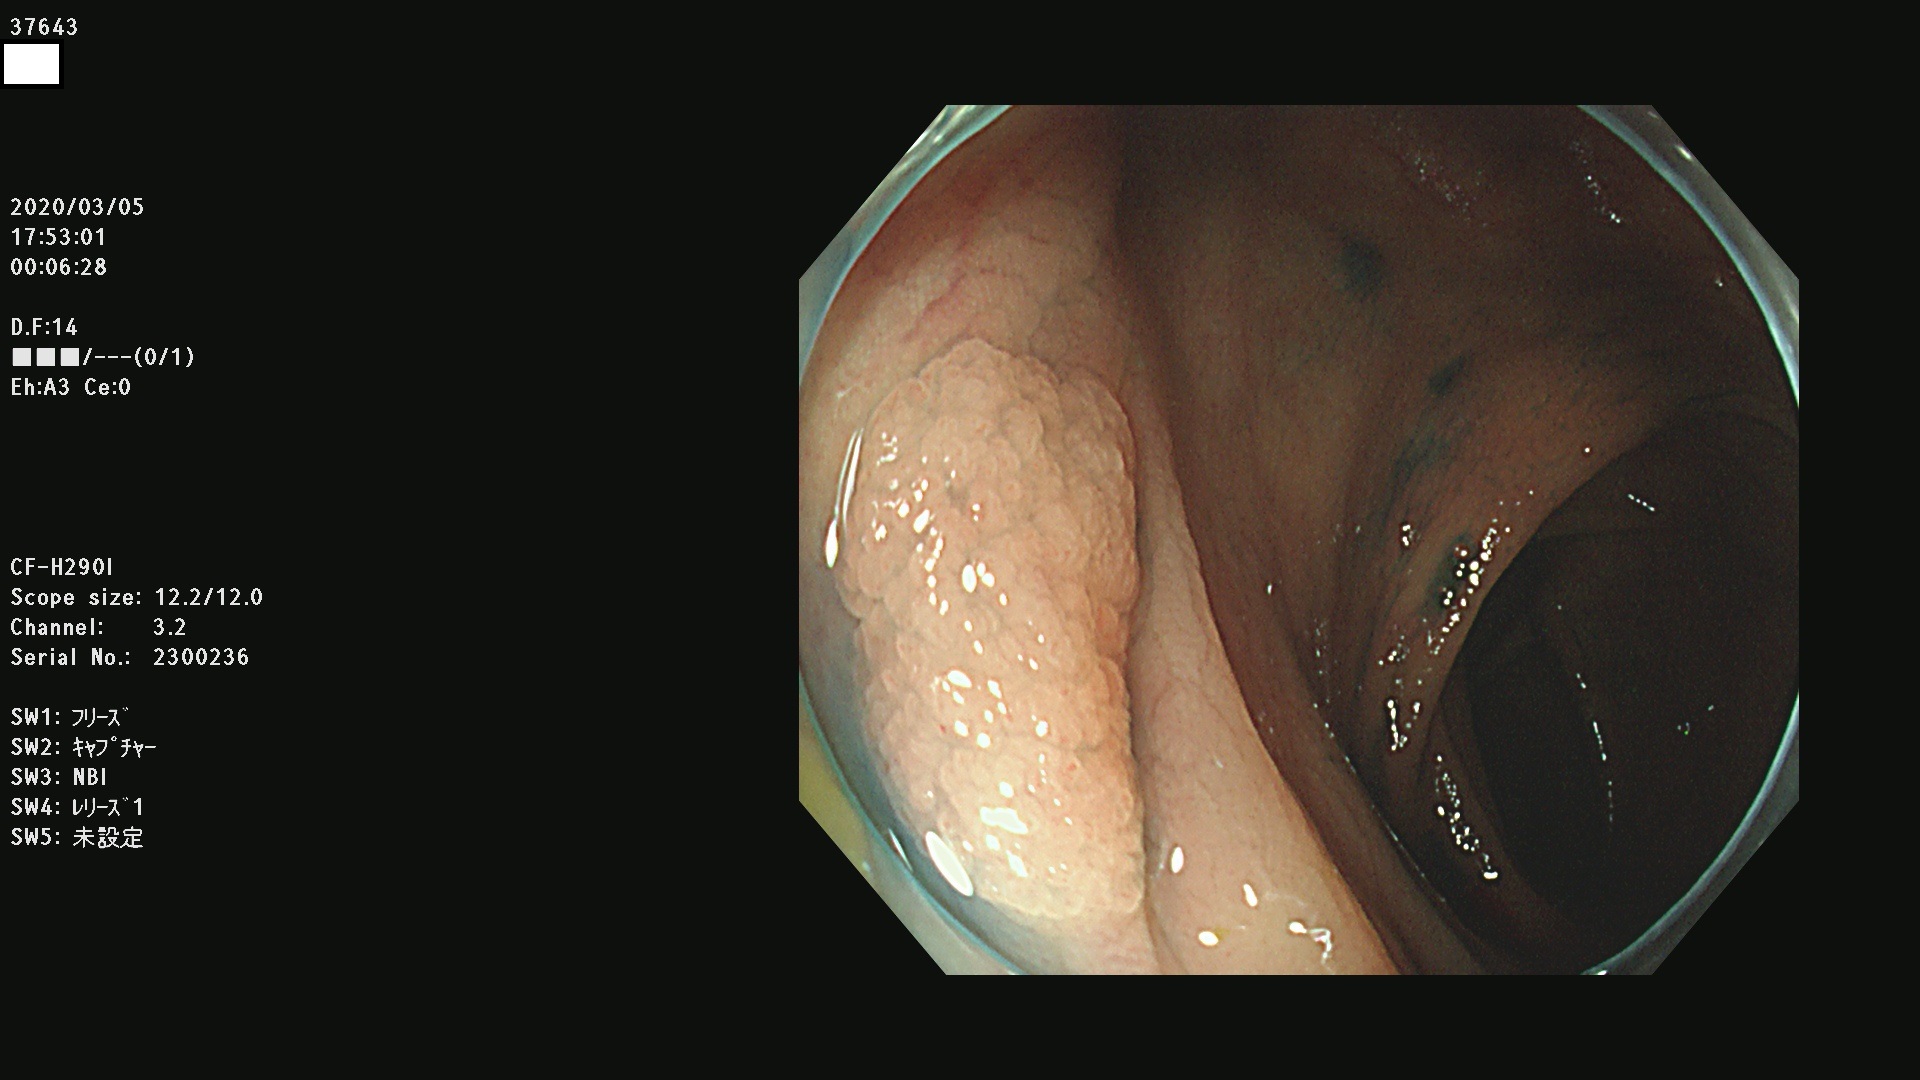

37600 37601 37602 37603 37604 37605 37606 37607 37608 37612 37614 37616 37618 37619 37620 37621 37622(SSAPのみ) 37623(SSAPのみ) 37624 37626 37627 37628 37629 37632 37633 37635 37636(SSAPのみ) 37639 37640 37641 37642 37643 37644 37647(SSAPのみ) 37648 37649 37650 37652 37653 37655 37657 37659 37660 37662 37664 37666 37668(SSAPのみ) 37670 37671 37672 37676 37677 37678 37679 37680 37682 37684 37685(SSAPのみ) 37686 37687 37688 37689 37690 37691 37692(SSAPのみ) 37693 37694 37695 37696 37697 37699

発見困難で危険性の高い平坦型病変(上記100名より抽出)